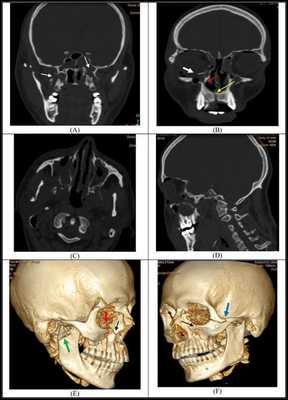

Симптоматика переломов костей средней зоны лица многообразна, поэтому для постановки точного диагноза требуется выполнение рентгенологической диагностики. Самым современным и точным методом является компьютерная томография . С её помощью челюстно-лицевой хирург имеет возможность точно определить локализацию линии разъединения костных фрагментов и тип перелома, выбрать наиболее адекватную и малотравматичную тактику лечения [11] .

КТ головы (3D-реконструкция). Перелом лицевого черепа (скуловой дуги) и перелом в области лобно-скулового шва.